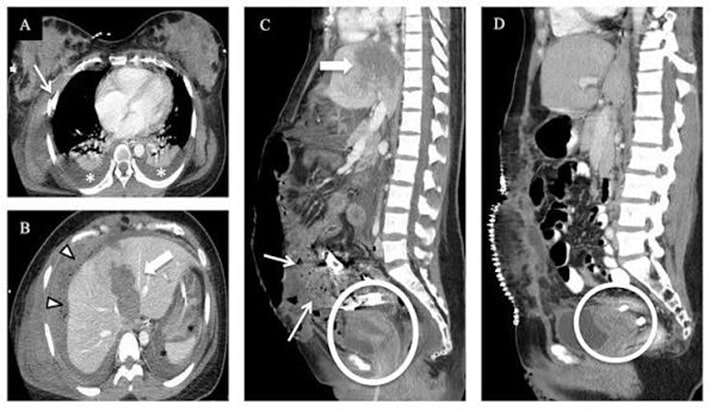

بررسی آسیبهای ناشی از تصادف یا ضربه

در بیماران دچار تصادف یا ضربه شدید، سی تی اسکن شکم میتواند خونریزیهای داخلی یا پارگی اندامها را با دقت بالا مشخص کند. این ویژگی، سرعت تشخیص و تصمیمگیری پزشک را بهطور چشمگیری افزایش میدهد.

آیا انجام سی تی اسکن شکم در بارداری خطرناک است؟

یکی از پرسشهای رایج در دوران بارداری، نگرانی از انجام سی تی اسکن شکم است. بسیاری از مادران باردار نگراناند که این روش تصویربرداری ممکن است بر جنین تأثیر منفی بگذارد. برای پاسخ به این سؤال باید چند نکته تخصصی را درباره ماهیت سی تی اسکن شکم و لگن بدون تزریق یا با تزریق بدانیم.

اشعه سی تی اسکن و اثر آن بر جنین

سی تی اسکن بر پایه تابش مقدار کنترلشدهای از اشعه ایکس انجام میشود. این اشعه برای بزرگسالان بیخطر است؛ اما در دوران بارداری، بهخصوص در سهماهه اول، ممکن است نگرانیهایی درباره تأثیر احتمالی آن بر رشد سلولی جنین وجود داشته باشد.

با این حال، مقدار اشعهای که در سی تی اسکن شکم استفاده میشود؛ در بیشتر موارد بسیار کمتر از حدی است که بتواند باعث آسیب شود. پزشک متخصص رادیولوژی همیشه قبل از انجام اسکن، میزان اشعه را با وضعیت بیمار تنظیم میکند تا خطری برای مادر یا جنین ایجاد نشود.

چه زمانی انجام سی تی اسکن شکم در بارداری ضروری است؟

در شرایط خاصی، ممکن است پزشک با وجود بارداری، انجام سی تی اسکن شکم و لگن را تجویز کند؛ بهویژه زمانی که خطر عدم تشخیص بیماری برای مادر بیشتر از خطر احتمالی اشعه باشد. برای مثال، در موارد زیر انجام سی تی اسکن میتواند حیاتی باشد:

- درد شدید شکم با احتمال آپاندیسیت یا پارگی روده

- خونریزی داخلی یا آسیب ناشی از تصادف

- بررسی سنگ کلیه در مراحل حاد

- تشخیص تومور یا عفونتهای شکمی خطرناک

در چنین شرایطی، پزشک معمولاً از سی تی اسکن شکم و لگن بدون تزریق استفاده میکند تا از مصرف مواد حاجب نیز جلوگیری شود.